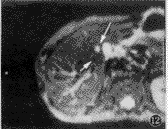

图11,12 男,47岁,结肠癌肝多发转移。图11为true-FISP T2WI,右肝近胆囊窝处见多个高信号结节影(箭头),难以区分是转移灶还是血管断面;图12为IR-EPI-ld T2WI,转移灶仍呈高信号(长箭头),血管断面变成低信号(短箭头)